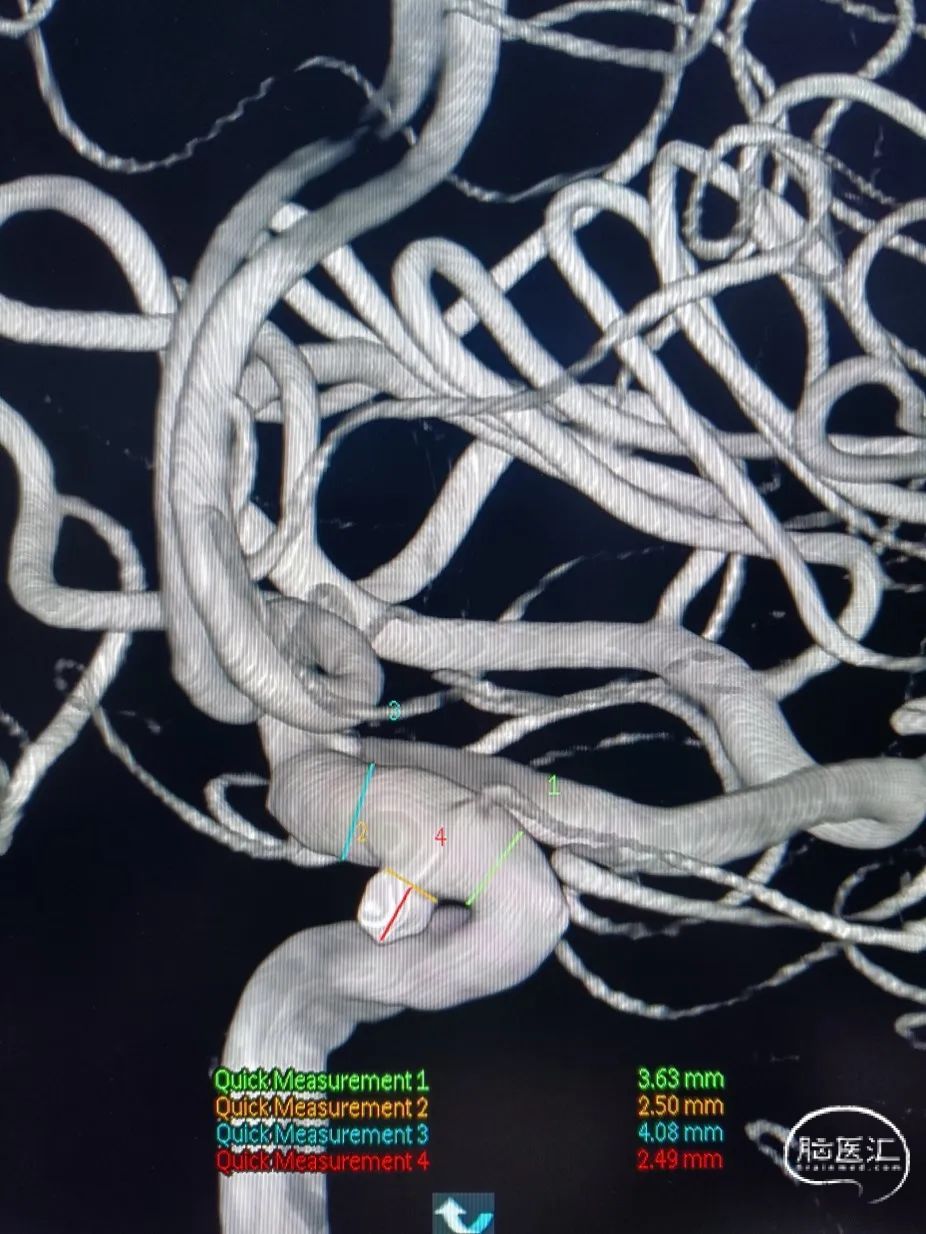

术前影像

术前3D:动脉瘤大小约2.52*2.34mm,颈宽约2.38mm,载瘤动脉近端约3.63mm,远端4.08mm。